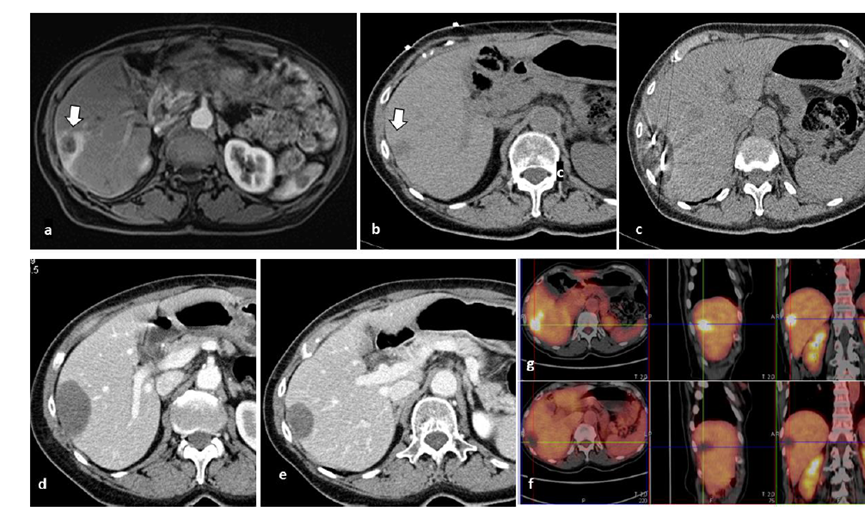

79 歲男性,肝轉(zhuǎn)移(結(jié)直腸癌)腫瘤的完全消融病例

( a ) 軸向 MRI 和 ( b ) 軸向 CT 顯示肝S8段有一個(gè)16mm的病灶,鄰近肝緣。( c )冷凍消融期間CT顯示放置了2個(gè)冷凍探針,低密度冰球包圍病灶。(d)術(shù)后1個(gè)月隨訪 CT顯示冰球?qū)?yīng)的壞死區(qū)域,未見復(fù)發(fā)。(e)術(shù)后6個(gè)月的CT,壞死區(qū)域縮小,未見復(fù)發(fā)。(f)與基線影像(g)相比,12個(gè)月后的FDG-PET/CT顯示未見FDG攝取。

62歲女性,肝轉(zhuǎn)移(卵巢癌)腫瘤的完全消融病例(a)軸向CT顯示病變位置毗鄰心臟和上腔靜脈(黑色箭頭)。(b)術(shù)中軸向CT掃描:使用三個(gè)冷凍探針。1個(gè)月后的軸向(e)和冠狀位(f)增強(qiáng)CT掃描顯示低密度區(qū)域,由于肉芽組織反應(yīng)引起的邊緣增強(qiáng)。